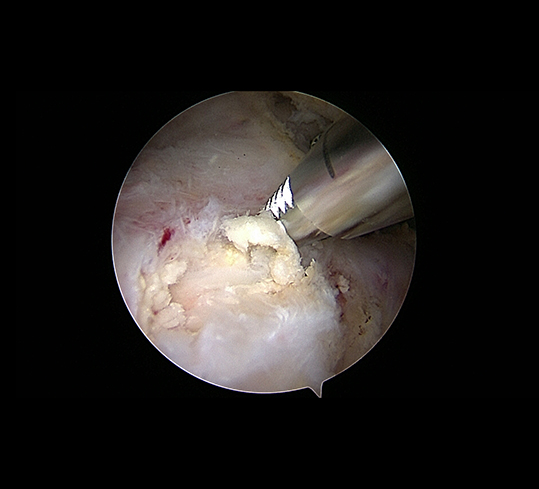

If this does not lead to the desired success and the symptoms persist, the calcium deposits can be removed arthroscopically - a gentle procedure that often leads to rapid relief of symptoms.